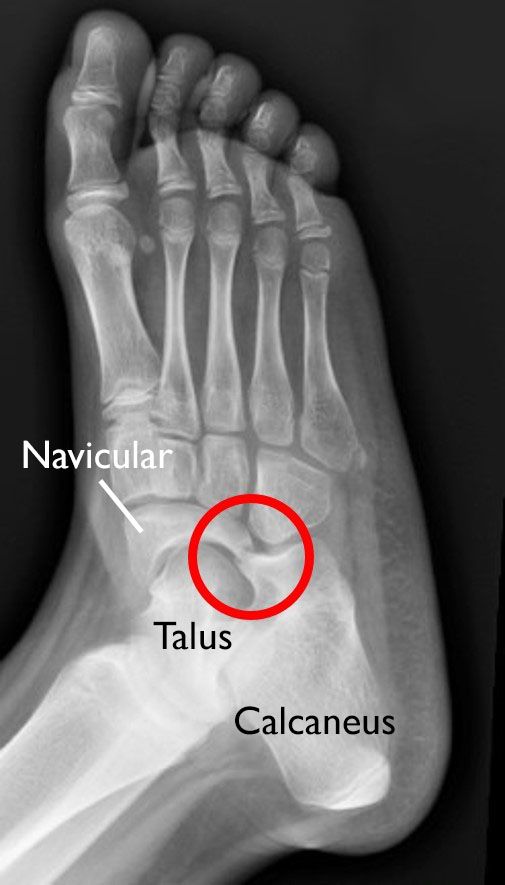

Tarsal Coalition OrthoInfo AAOS